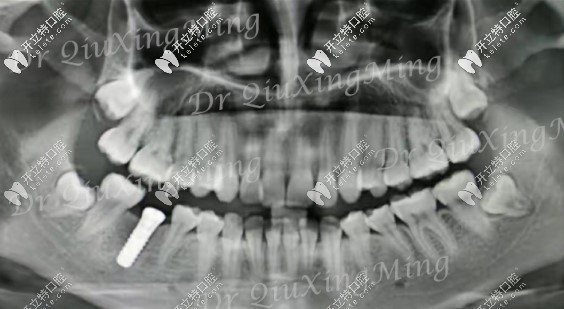

朋友的牙片▼

第1磨牙缺失幾年后的ct